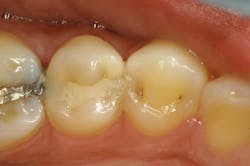

After removing a two-week-old provisional, it’s a rare day that we don’t experience some minor inflammation of the soft tissues. Even with the best prototypes/provisionals and meticulous oral hygiene, gingival tissues will bleed, exude fluids, and generally cause problems when isolating teeth for adhesive delivery. With a direct composite, the existing decay is an irritant, and the best isolation device will not address the bleeding tissue adjacent to an extensive class II cavity.

With an inverted rubber dam, however, bleeding becomes a nonissue and allows the clinician to focus on preparation design, pulpal protection, adhesive strategies, and restoration placement—all in a clean and well-sealed environment.3 “Beating the blood” need not be your approach when one of dentistry’s least-used gems is close at hand (figures 6 and 7).